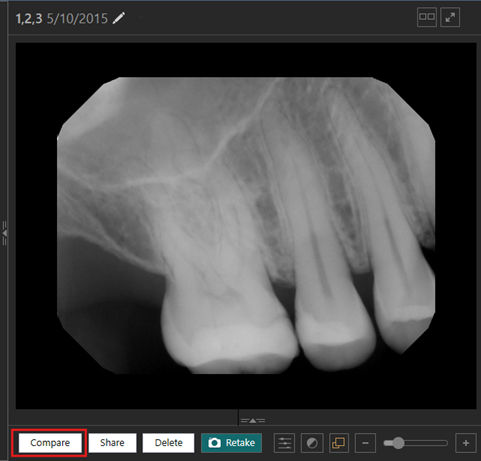

Comparing up to Six Images at Once

You can now compare up to six images (intraoral or extraoral; X-ray or photo) at once. This enables clinicians to flexibly compare multiple images side-by-side while maintaining visual context and efficiency.

To compare multiple images

1. While viewing an image, click Compare.

The image is loaded in the first comparison frame, the images for the same tooth range appear on the filmstrip, and there are options on the lower toolbar.

2. In the lower-left corner, select the icon that corresponds to the desired number of frames: two, four, or six.

3. Select each image on the filmstrip in turn to add that image to the comparison frame in the viewing area. Each frame with an image has color and number indicators, and the corresponding image on the filmstrip has the same color and number indicators.

Notes:

- The filter icon (for filtering which images appear on the filmstrip) is now a funnel (previously, it was a pencil icon).

- To remove an image from a comparison frame in the viewing area, click the corresponding trash can icon.

- The tools in the lower-right corner have number and color indicators that match the selected frame.

4. When you are done comparing images, click Finish Comparison.